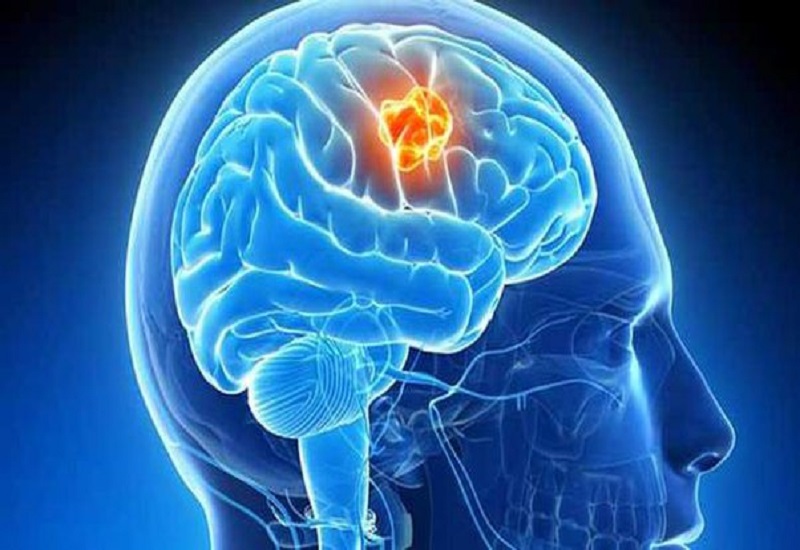

मूत्र की जांच से भी पता लगाया जा सकता है Brain Tumor, अध्ययन में हुआ खुलासा

मस्तिष्क के कैंसर का पता लगाने में इस्तेमाल होने वाले प्रोटीन से ट्यूमर का पता लगाने के लिए आवश्यक आक्रामक जांच की आवश्यकता कम हो सकती है

टोक्यो। वैज्ञानिकों ने मूत्र में एक प्रमुख झिल्ली प्रोटीन की पहचान करने के लिए एक नए उपकरण का इस्तेमाल किया है जिससे यह पता चलता है कि मरीज को मस्तिष्क का ट्यूमर है या नहीं। झिल्ली प्रोटीन ऐसे प्रोटीन होते हैं जिनसे या तो जैवझिल्लियां निर्मित होती हैं या जो इन जैव झिल्लियों से जुड़ने या आर-पार जाने में सक्षम होते हैं। अध्ययन के अनुसार, मस्तिष्क के कैंसर का पता लगाने में इस्तेमाल होने वाले प्रोटीन से ट्यूमर का पता लगाने के लिए आवश्यक आक्रामक जांच की आवश्यकता कम हो सकती है और ट्यूमर के शुरुआती स्तर पर ही पता चलने की संभावना बढ़ सकती है ताकि उसे सर्जरी से हटाया जा सके।

अध्ययन में कहा गया है कि जापान के नगोया विश्वविद्यालय के इस अनुसंधान का अन्य प्रकार के कैंसर का पता लगाने के लिए संभावित असर हो सकता है। यह अध्ययन पत्रिका 'एसीएस नैनो' में प्रकाशित हुआ है। हाल फिलहाल में कई प्रकार के कैंसर का शुरुआती स्तर पर पता चलने से कैंसर पीड़ितों के बचने की संभावना बढ़ गयी है। हालांकि, ब्रेन ट्यूमर से पीड़ित लोगों के जीवित बचने की दर में पिछले करीब 20 साल से कोई बदलाव नहीं आया है। इसकी मुख्य वजह संभावित रूप से देर से पता चलना हो सकती है।

अध्ययन के अनुसार, किसी व्यक्ति के ब्रेन ट्यूमर से पीड़ित होने का संभावित संकेत उनके मूत्र में ट्यूमर से संबंधित बाह्य कोशिका (ईवी) की उपस्थिति है। इसमें कहा गया है कि ईवी सूक्ष्म आकार की कोशिका होती हैं जो कोशिका से कोशिका के बीच संचार समेत कई कार्यों में शामिल होती हैं। चूंकि ब्रेन कैंसर के मरीजों में पाए जाने वाले इन ईवी में विशेष प्रकार के आरएनए और झिल्ली प्रोटीन होते हैं तो इनका इस्तेमाल कैंसर का पता लगाने में किया जा सकता है।